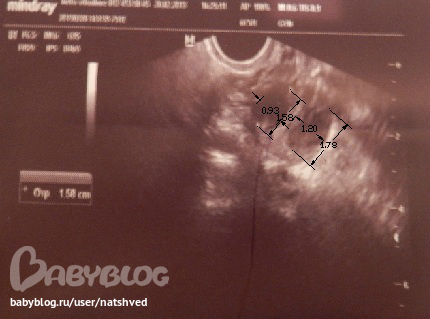

Сходила на узи

сегодня 23дц, 10дпо:

эндик 9,6мм

ЛЯ ЖТ 15,8мм + ЖТ 17,8мм

14дц, 1дпо:

эндик 8,4мм

ЛЯ ЖТ 13,5мм + ЖТ 16,1мм